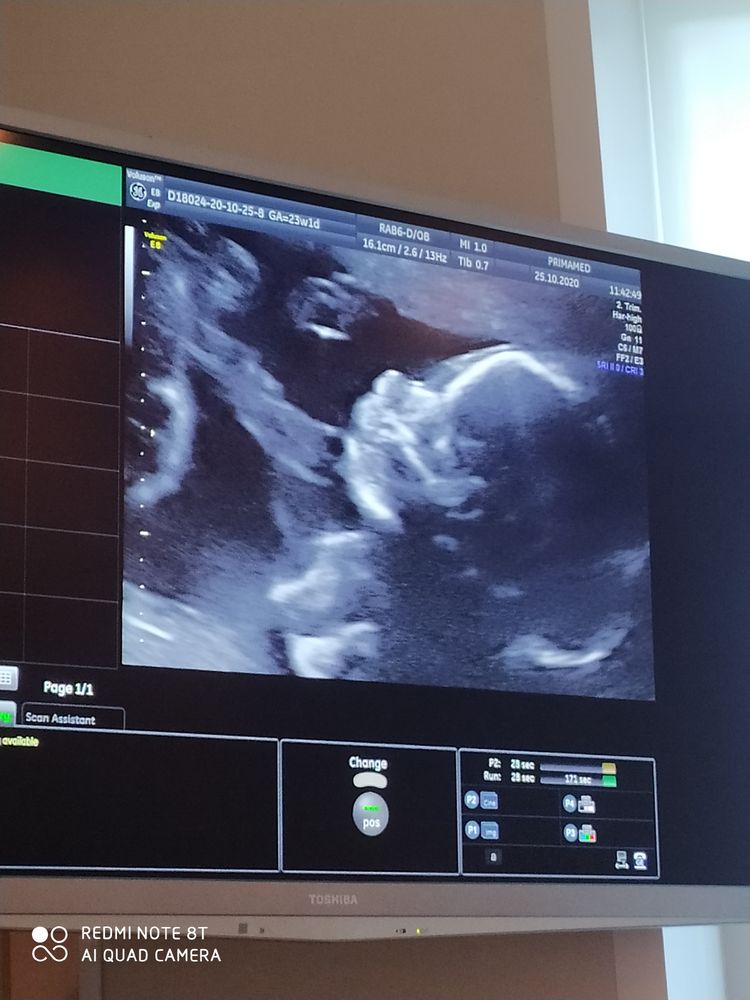

23 недели полет нормальный))

25.10.2020

Какое чёткое узи красивое! Уже больше полсрока преодолели